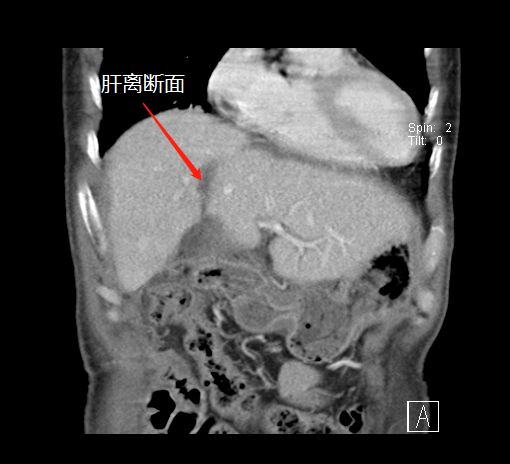

術前,左肝體積很小

第一次術后,結(jié)扎門靜脈劈開肝臟

左肝增生,第二次手術切除腫瘤

“9月底,在第一階段手術中,我們先將患者的右側(cè)門靜脈結(jié)扎(肝的血液供應通過門靜脈和肝動脈進行),保留肝動脈、肝靜脈和膽管的完整性,然后沿肝中裂將肝臟的左右葉徹底劈開?!睋?jù)胡偉介紹,人體肝臟具有很強的再生功能,結(jié)扎門靜脈右支后左側(cè)肝臟由于過量的血液供應短期內(nèi)迅速增大;同時將患者的左右肝臟離斷,降低了腫瘤侵犯左側(cè)肝臟的可能。

第一次手術后

經(jīng)過20天左右的“養(yǎng)肝”,經(jīng)CT復查顯示,患者的左側(cè)肝臟體積已增長至42.8%,這時候,也就達到了我們說的“養(yǎng)大好肝、再切病肝”,因為此時好肝已經(jīng)足以維持患者身體的運轉(zhuǎn)需要。